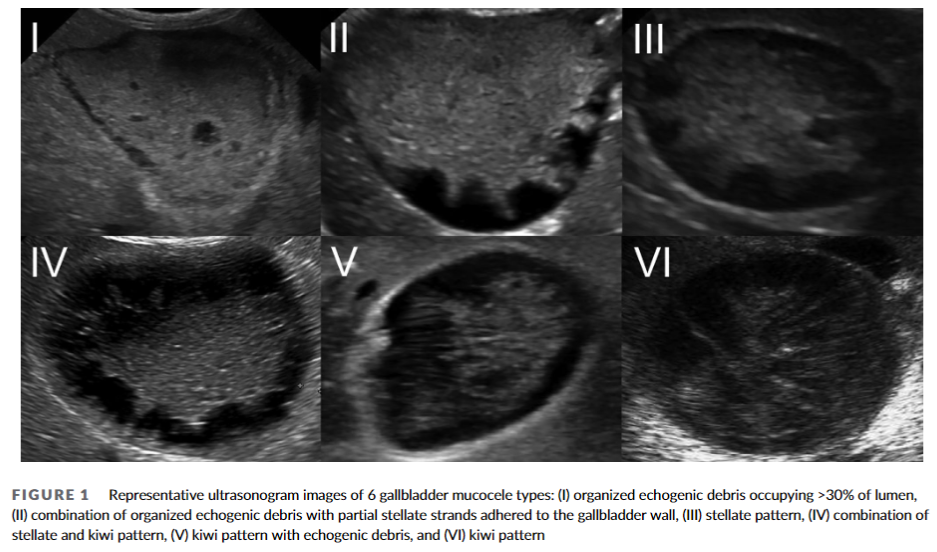

담낭점액종의 초음파 소견과 임상증상의 관계에 관련한 논문,

기존의 점액종 type 구분은 동일하나

확실히 type이 높아질 수록 임상증상이 있는 비율이 높아지고 있다.